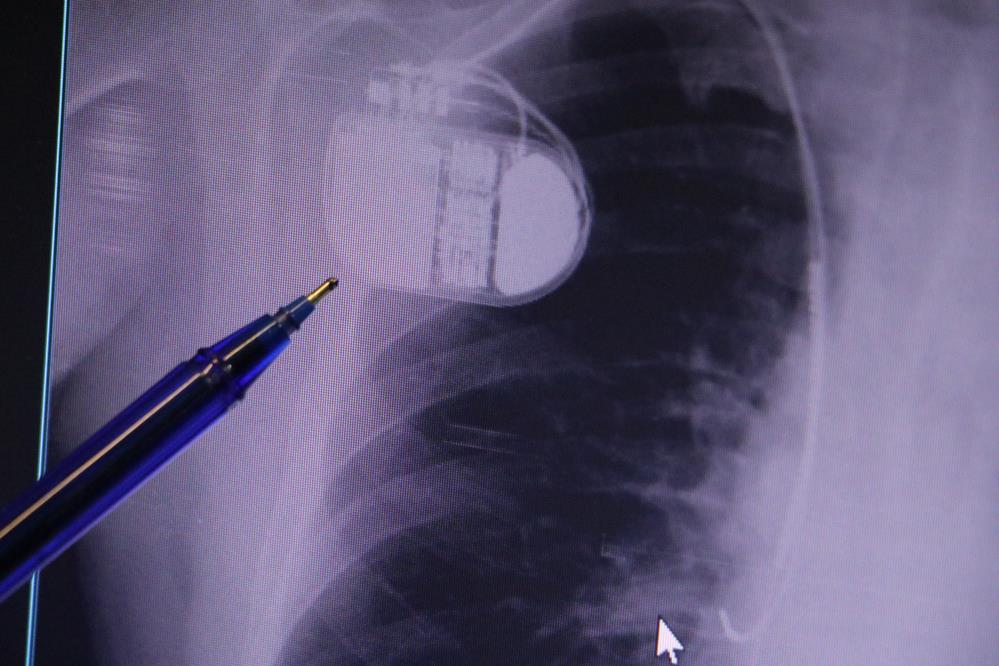

Kalp pilleri ile MR cihazına girilebileceğini belirten Erdoğu, "Çok büyük bir ameliyat değil ama yine de ciddi bir cerrahi işlem. Kalp pili, tıpta son 30 yılda yaşanan gelişmelerden en büyüğü. Bir bilgisayarın küçültülüp insan vücuduna konulmuş hali aslında. İnsan ömrünü ciddi oranda uzatan bir tedavi. İnsanlar bir şokla hayata tutunurken, pil olmasaydı öleceğini düşündüğümüz birçok hastamız var. Kalp pilinin bu özelliği, uygun hastalarda ciddi oranda ani ölümü engelliyor. Hastanın başına gelecek bir kalp durması durumunda yanında bir sağlıkçı yoksa, onun ritmini düzeltecek defibrilatör cihazı yoksa hastayı hayatta tutmak mümkün değil. Uygun endikasyonlarda kalp pili olduğu zaman, pil hastaların ritmini algılıyor ve acilde yapılan şoklamayı yaparak hastayı hayata döndürüyor. Kalp pillerinde yeni teknolojilerle MR'a girmek mümkün, tomografiye zaten girebiliyorlar. Tarama cihazlarından geçmelerini uygun görmüyoruz. Bu tarz durumlarda hastalarımız 'kalp pilim var' dediğinde muaf tutuluyorlar. Kalp pilleri ciddi teknolojik cihazlardır. Vücudun içindeki titreşimi, örneğin mikser kullanmak, kolunu sallayacak herhangi bir eylem kalp pilinde olumsuz etki oluşturabilir. Soğuk havalarda vücutta oluşan ciddi titremeler kalp pilinin hafızasını karıştırıp kalbin durduğunu düşündürebilir ve gereksiz şoklama yapabilir. Bu tarz kişilerin soğuk havalarda daha temkinli olması gerekir" diye konuştu.